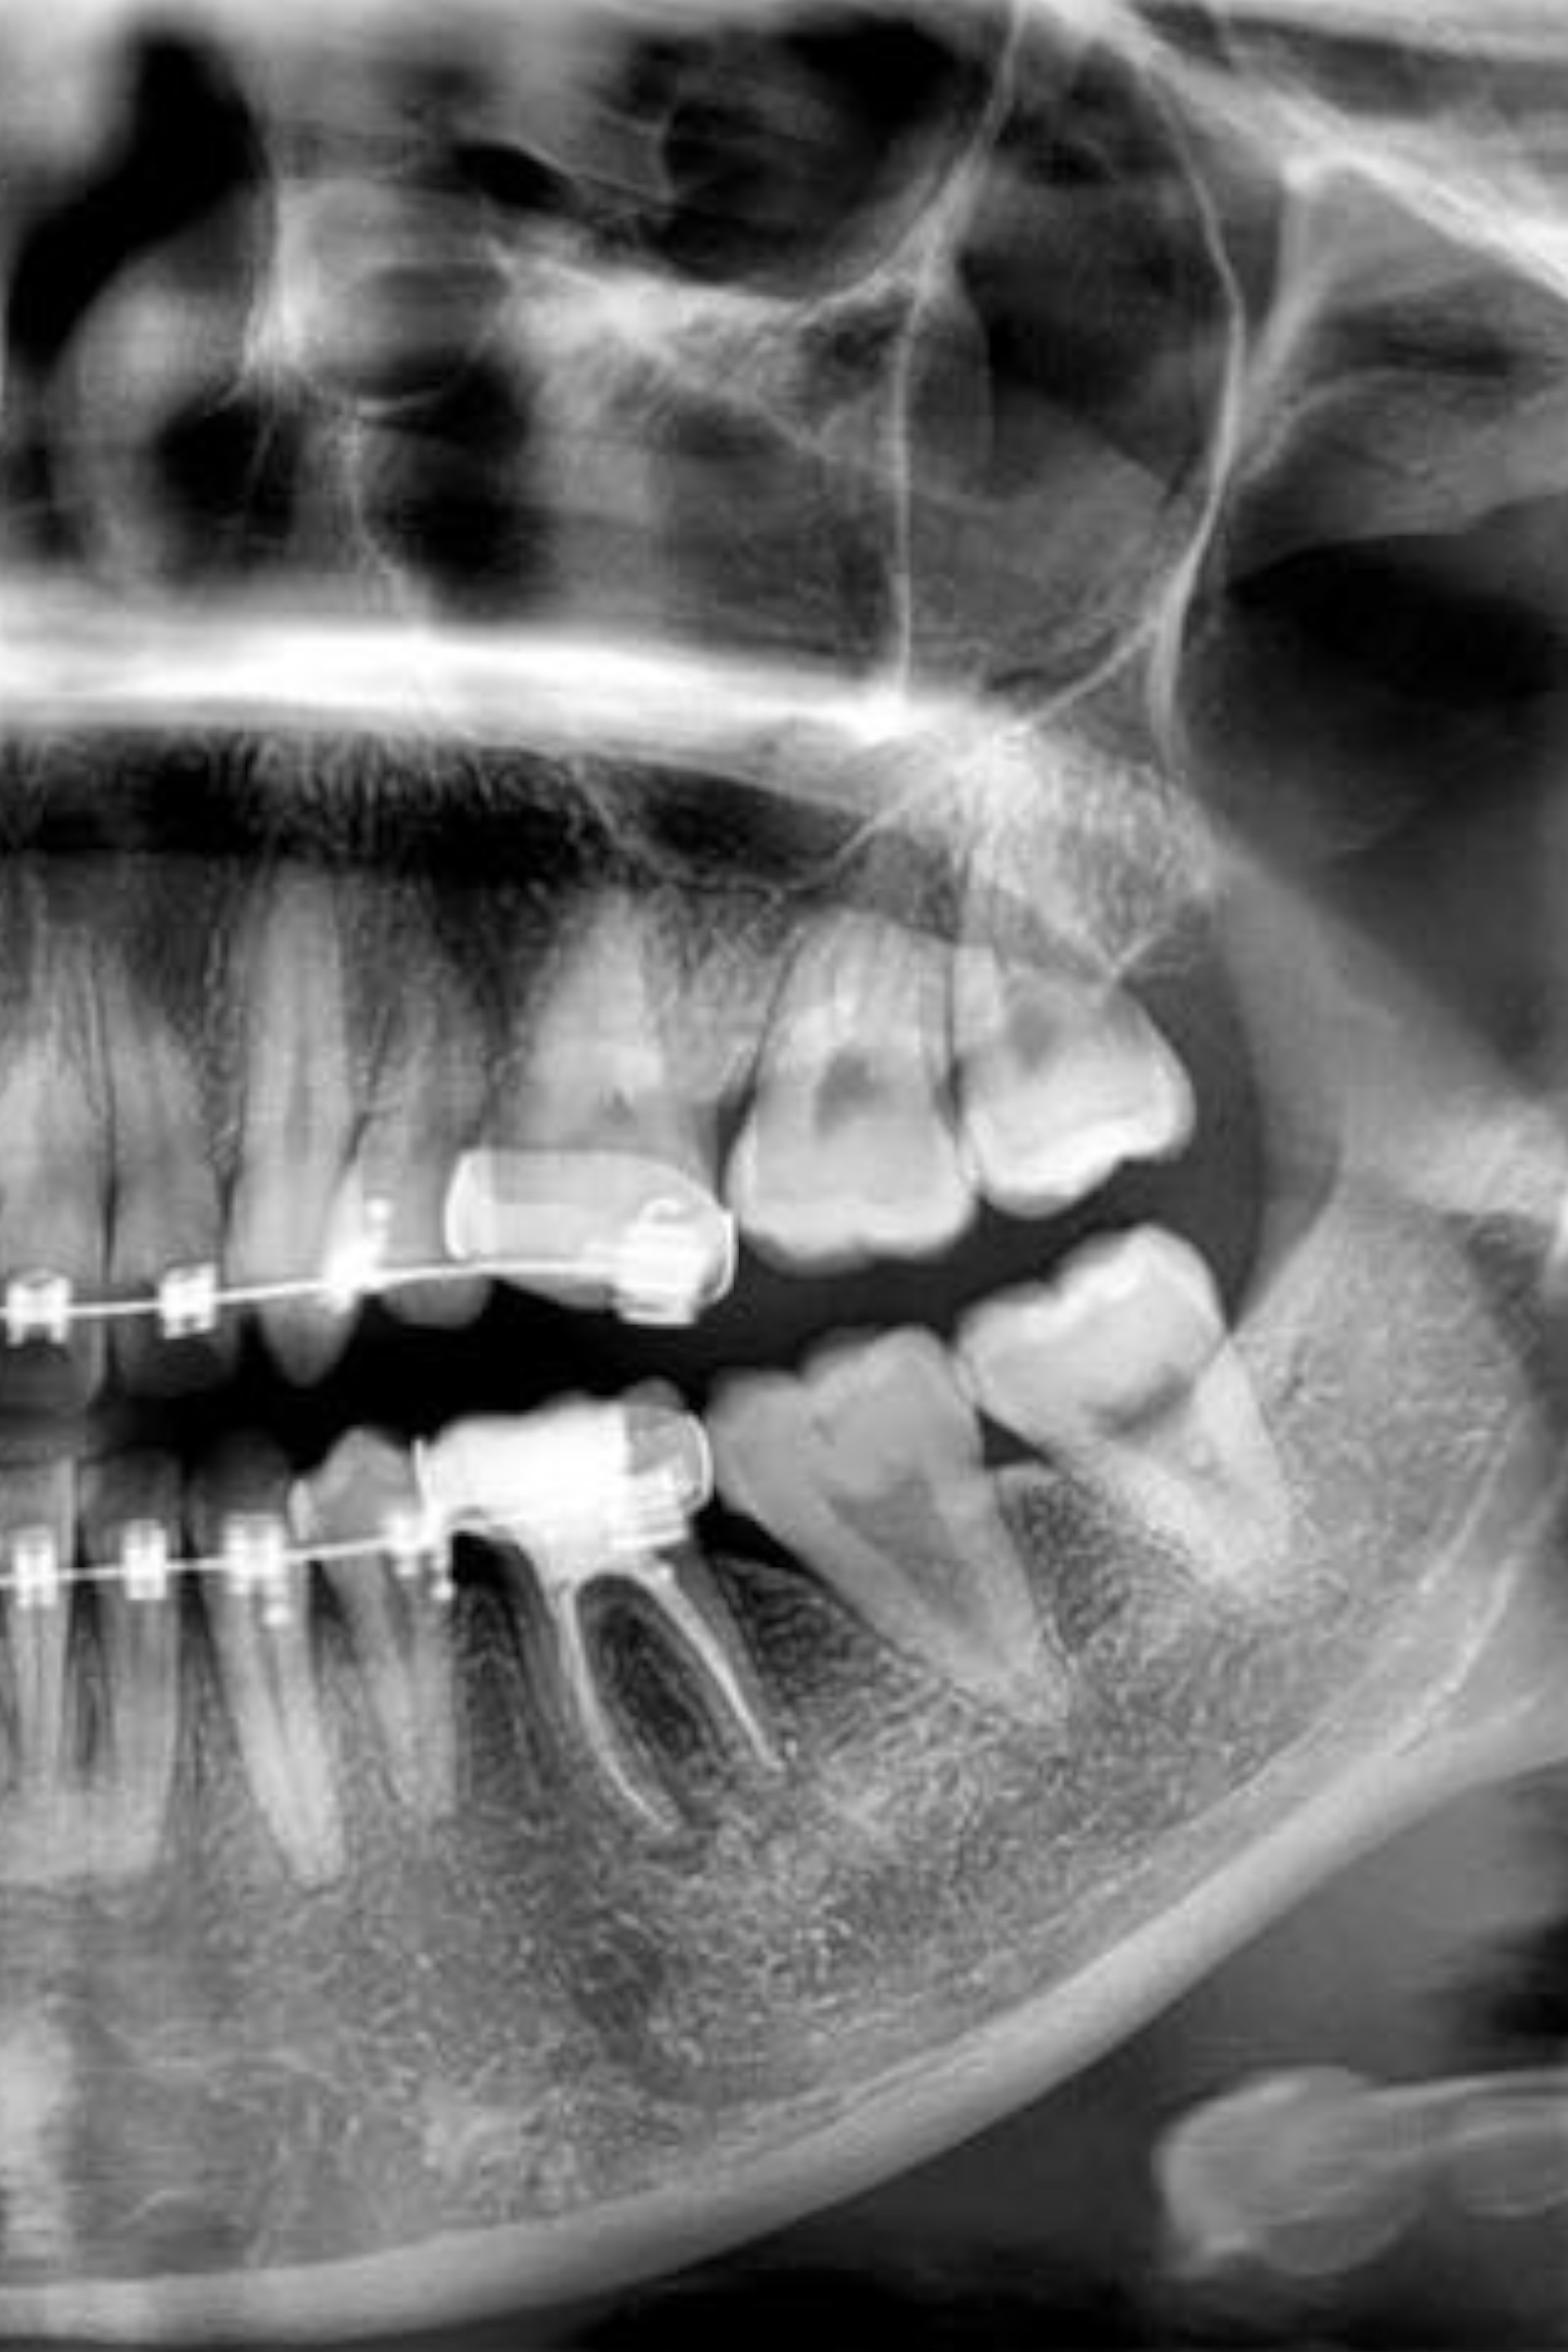

RADIOGRAFIAS DIGITALES

La radiografía es un complemento de diagnóstico indispensable en la rutina de cualquier especialidad odontológica.

En Dentalec enfocados en una mejor atención hacemos un esfuerzo para brindar a nuestros pacientes un diagnóstico rápido, oportuno y de vanguardia, para esto contamos con un sistema de radiología digital el cual tiene grandes ventajas sobre la radiología convencional.

- Manipulación de imagen: se pueden hacer mediciones por medio de reglas digitales, aumento en las áreas deseadas, envío de archivos digitales.

- Expedientes clínicos completos. Las radiografías digitales son fácilmente almacenables a través de formatos digitales, lo cual se convierte en una herramienta de diagnóstico para comparar imágenes anteriores con las mas recientes, sin que estas sufran deterioro.

- Fidelidad: En la actualidad estudios comprueban que las radiografías digitales son de calidad igual o mejor que las convencionales para la detección de lesiones bucales.